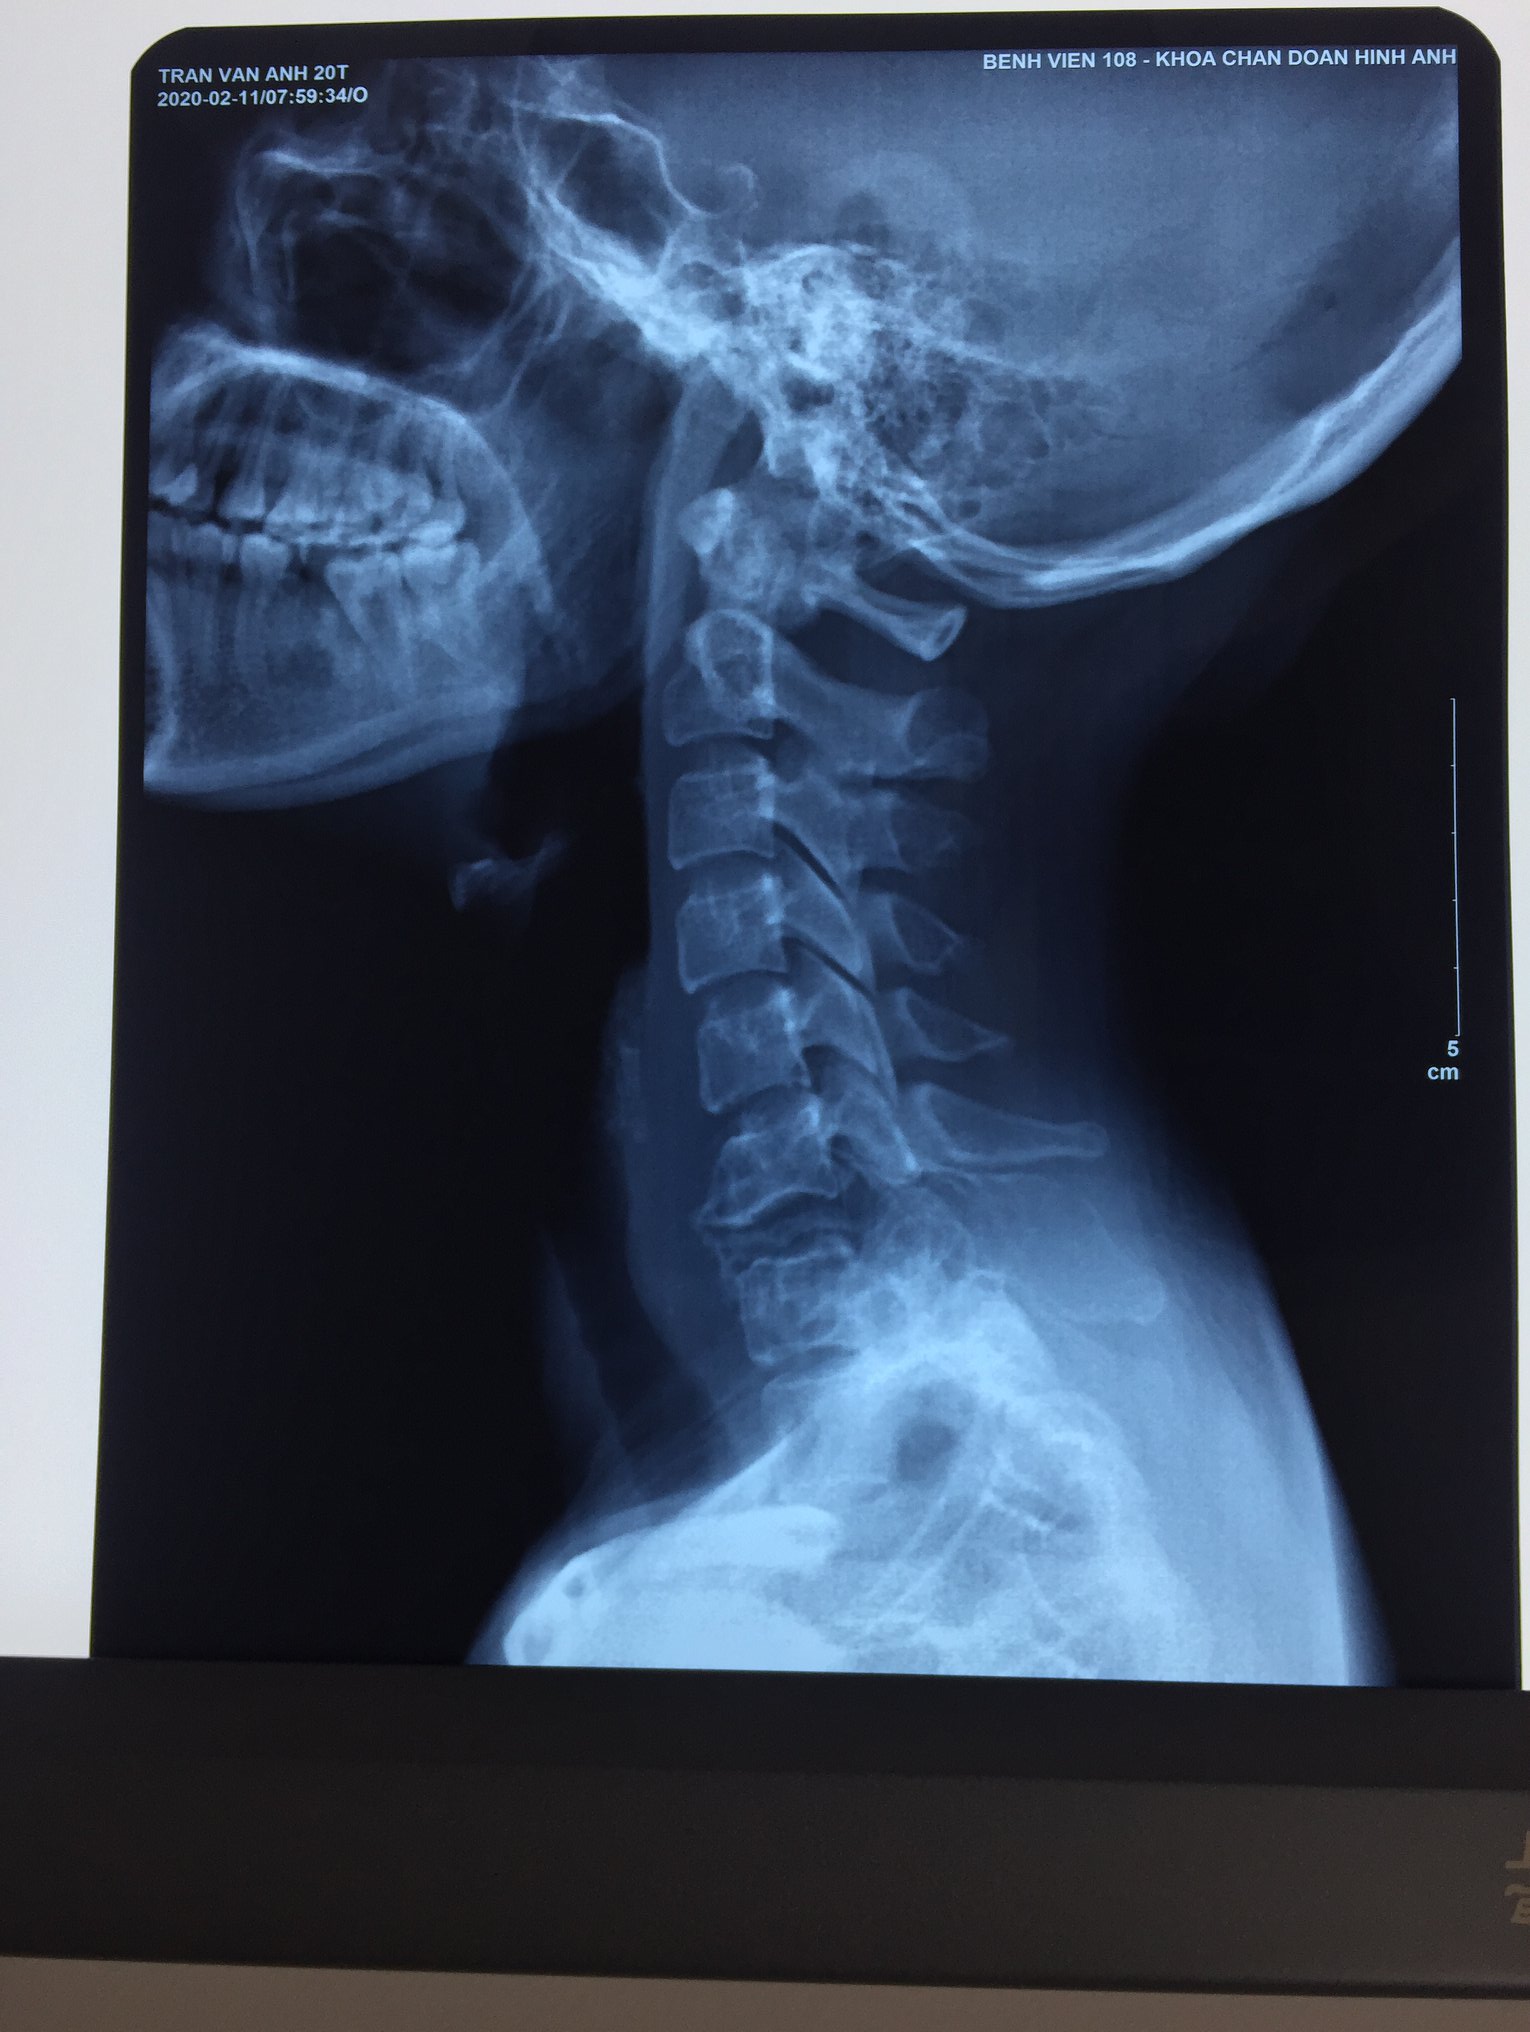

Hình ảnh Xquang: gãy xẹp hoàn toàn thân đốt C7, tiêu xương và phì đại gai sau C7